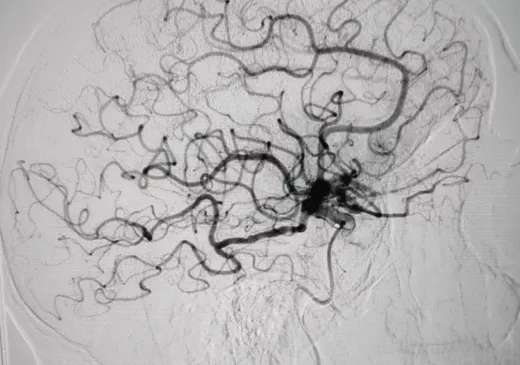

La sala de radiologia intervencionista durant la realització d'una trombectomia mecànica a un pacient que havia patit un ictus isquèmic.

En aquestes dues imatges, podem veure com queda afectada la circulació arterial arran d'un ictis isquèmic i com es recupera després del tractament endovascular.